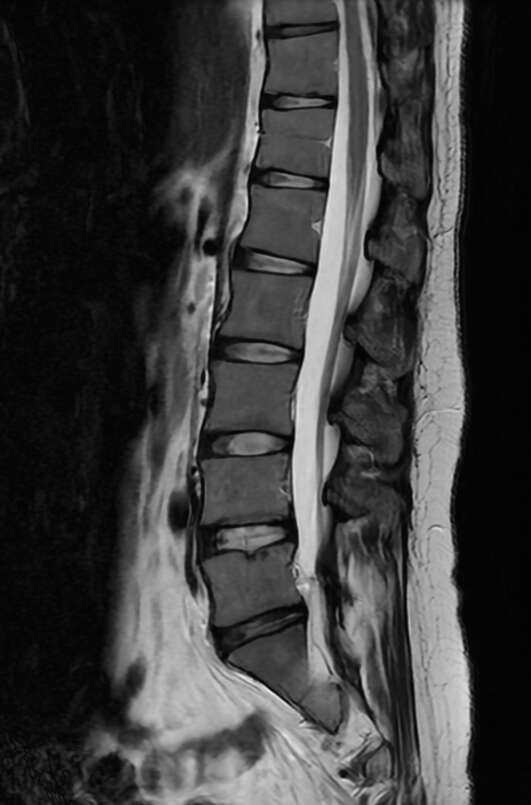

●脊髄腔造影(ミエログラフィー)/ 神経根ブロック

腰背部から針を刺し、脊髄腔にヨード造影剤を注入し、脊髄腔の形状や交通を観察する検査です。

脊柱管狭窄症や椎間板ヘルニアの診断に役立ちます。ミエログラフィーに引き続いて、痛みの原因部位に痛み止めを注射する神経根ブロックを続けて行う場合もあります。

腰部脊髄造影

脊髄腔は腰椎の後ろ側に位置し、頭から腰まで「丸い管」のように繋がっています。椎間板ヘルニア等があると脊髄腔が圧迫され、丸い形が窪んだ状態で描出されます(左図の赤矢印)。